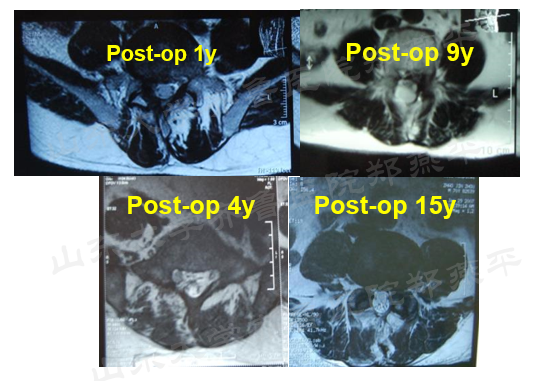

后正中入路椎旁肌剥离后的影像学表现

腰椎退变性疾病后正中入路术后随访结果

肌肉萎缩程度影响因素主要包括牵开时间、剥离范围、脊神经后根中间支的机械性牵拉及热损伤程度、肌肉动脉血供损伤程度及术后制动等有关。

多裂肌退变与慢性腰痛密切相关,当脊柱突然失平衡时,多裂肌的收缩明显早于最长肌和腰髂肋肌。临床上慢性腰痛的患者,多裂肌的收缩较正常人明显延迟,且多裂肌萎缩,常伴有纤维化和脂肪沉积。这些都需要医生在临床工作中注意。